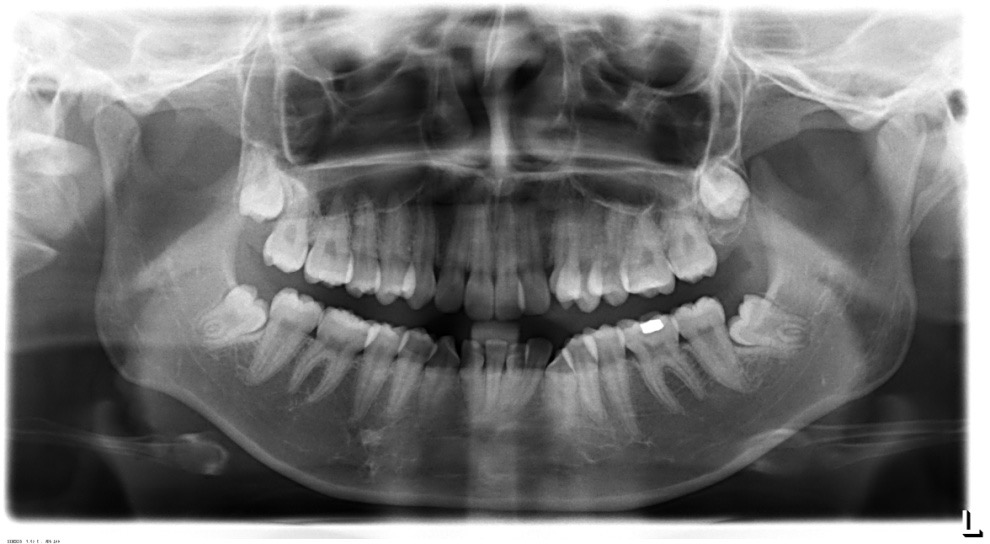

全景片

Post-TXPRE-TXPost-TXNormFMIA°47°57.555.0SNA°77.7°76.883.0SNB°70.2°73.780.0ANB°7.5°3.13.0FMA° 29.828.026PFH/AFH70.5°65.970Z Angle°50.3°64.477U1-FH113.0103.7110.0 IMPA°103.291.197.0U Lip tos’ line6.3 mm3.25.0L Lip to s’ line3.9 mm1.03.0OP-FH1212.615

牙根基本平行,未见牙根吸收